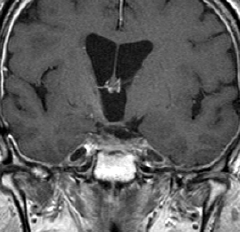

この子の症状は頭痛だけ。両親はなぜ気づかなかったのかと疑問を持ちますが,巨大になるまで症状が出ないこともあるのです。左のCTで腫瘍の周囲にバラバラと白い点状の石灰化があるので診断できます。左の視床下部から発生したクラニオでした。開頭手術しますが超高難易度です,怖いです (┯_┯) 複数回開頭手術になりましたが結果的に全摘出できています (by Dr 山本哲哉)。